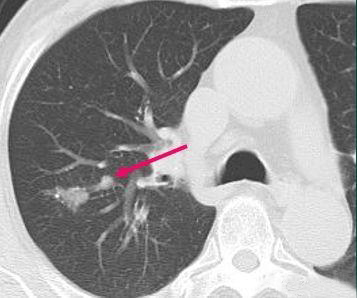

这是一位67岁男性病人,2013年体检发现右肺分叶状实性结节:

这个病人没有症状,结节比较光滑,会不会是结核球?我们不急于定论,先利用设备的强大后处理功能把图像放大后,观察到两个细节:

肺门侧有一个小结节,首先考虑淋巴结(局部转移),同时结节的远侧带一点光滑的小尾巴,这提示早期转移,淋巴浸润的可能,最符合小细胞肺癌的特点。进一步给病人做了增强扫描,显示这个小结节呈轻度强化(小细胞肺癌大多乏血供,多呈轻度强化),这就不应该直接手术了,需要先穿刺明确病理,因为如果是小细胞肺癌,转移早,进展快,手术不能获益(只有大约5%的局限期小细胞肺癌可以手术)。